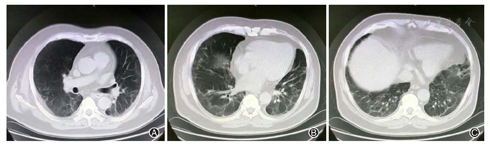

患者,男,56岁,因发热、咳嗽、咳痰伴活动后胸闷3 d于2019年9月10日入院。患者3 d前无诱因出现发热,体温在38 ℃左右,无畏寒、寒战,无盗汗,发热无明显规律性,伴咳嗽,咳少许黄白痰,无胸痛、咯血,伴胸闷、憋气,活动后加重,无消瘦,无头晕、恶心、呕吐,门诊行胸部CT考虑双肺感染性病变,为进一步诊治收住院。患者入院的20 d前在日本出差时出现咽痛,自服感冒药物(具体不详)后好转。既往有“冠心病、高血压”病史4年,2015年行冠脉造影示冠状动脉肌桥,无吸烟史,无禽类、粉尘、工业毒物接触史。体格检查:体温36.5 ℃,脉搏84次/min,呼吸23次/min,血压137/75 mmHg(1 mmHg=0.133 kPa),神志清,全身皮肤无皮疹,口唇发绀,双肺呼吸音粗,双下肺可闻及湿性啰音,心率84次/min,律齐,未闻及杂音。腹软,无压痛、反跳痛,双下肢无浮肿,四肢肌力正常。入院后查动脉血气分析(未吸氧):pH为7.374,二氧化碳分压为39.4 mmHg,氧分压为52.6 mmHg,血氧饱和度为84.8%,乳酸为1.1 mmol/L;血常规:白细胞计数为7.68×109/L,中性粒细胞百分比为 72.1%,淋巴细胞百分比为17.2%,红细胞计数为4.47×1012/L,血沉为16 mm/h;血生化:白蛋白为36.3 g/L,葡萄糖为6.44 mmol/L,乳酸脱氢酶为284 U/L,C反应蛋白为30.9 mg/L,三酰甘油为2.25 mmol/L;血凝常规:纤维蛋白原含量为4.67 g/L;肺肿瘤标志物CYFRA21-1为11.3 ng/ml;降钙素原为0.052 μg/L;病原学检查:半乳甘露聚糖试验(GM试验)为0.38 μg/L;痰细菌培养、真菌涂片、结核菌涂片阴性;肺炎支原体抗体、衣原体抗体、呼吸道合胞病毒抗体、出血热病毒抗体、真菌葡聚糖、巨细胞病毒核酸检测均阴性;免疫相关:抗核抗体(ANA)、抗环瓜氨酸肽抗体(CCP)、抗中性粒细胞胞浆抗体(ANCA)均阴性;机体细胞免疫评价正常;尿常规、大便常规、肌钙蛋白、脑钠肽均正常;乙肝表明抗原、丙肝抗体、梅毒抗体、HIV抗体均阴性;心电图示窦性心律、心电轴中度左偏、ST-T异常;胸部CT考虑双肺感染,建议治疗后复查,心影饱满,冠脉钙化,两侧胸膜略增厚(图1A~C)。入院后给予经鼻高流量湿化氧疗(氧浓度50.0%,氧流量50 L/min),美洛西林舒巴坦(2.5 g,1次/12 h)联合左氧氟沙星(0.6 g,1次/d)抗感染,奥司他韦胶囊(75.0 mg,2次/d)抗病毒,多索茶碱(0.3 g,1次/d)扩张支气管,溴己新(4.0 mg,2次/d)止咳化痰,低分子肝素钠(5 000 U,ih,1次/d)抗凝,硝苯地平缓释片(10.0 mg,2次/d)降压治疗,患者体温逐渐降为正常,但活动时胸闷无改善,经皮血氧饱和度在95.0% 左右(上述氧疗情况下),考虑抗感染解痉平喘治疗效果不佳,不除外间质性肺病,遂于9月14日加用甲泼尼龙(40.0 mg,1次/12 h)静滴,自觉症状略有好转,于9月17日复查胸部CT示双肺片状影较前增多(图2A~C),提示疾病进展,与患者及家属沟通后于9月17日行床旁支气管镜检查,镜下见左右肺各叶段支气管通畅,黏膜轻度充血,可见少量白色泡沫样分泌物,未见狭窄、出血及新生物(图3),于右肺下叶后基底段行肺泡灌洗及透壁肺活检,肺泡灌洗液(BALF)细胞分类示淋巴细胞百分比为63.0%,中性粒细胞百分比为24.0%,巨噬细胞百分比为8.0%,上皮细胞百分比为5.0%;BALF细菌、真菌涂片和培养均阴性;BALF结核菌涂片、结核菌核酸扩增检测(Gene Xpert)均阴性;BALF脱落细胞学检查阴性;BALF-GM试验0.55 ng/ml;BALF病原微生物宏基因组检测(NGS)示产黑色素普雷沃菌(序列数12)、龋齿罗氏菌(序列数7)、简明弯曲杆菌(序列数1);支气管镜肺活检病理考虑肺间质纤维化(图4)。患者对治疗反应不佳,为排除肿瘤于9月20日行正电子发射计算机断层显像(PET-CT)示双肺多发斑片影、结节灶,大部分见支气管充气征,部分结节边缘见分叶和毛刺,SUVmax 6.4,考虑感染性疾病,霉菌感染可能性大,肉芽肿性炎和MALT淋巴瘤不除外(图5)。请北京协和医院专家会诊,考虑ILD,不除外结缔组织病相关,建议加大甲泼尼龙(80.0 mg,1次/8 h)用量,升级抗生素为美罗培南(1.0 g,1次/8 h),完善肌炎谱13项示抗Jo-1抗体阳性,最终诊断为抗Jo-1抗体综合征,加用环磷酰胺(0.4 g,1次/周)静滴8次,并逐渐减少甲泼尼龙用量,患者胸闷症状明显好转,2019年11月18日复查胸部CT示肺内病变较前明显吸收好转(图6A~C),随访1年,病情稳定。